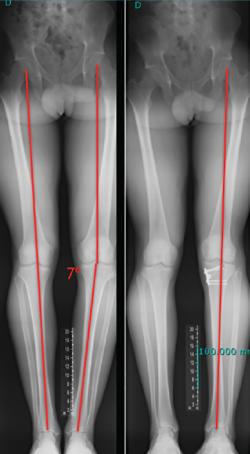

Figura 1. Imagen radiológica que permite identificar una técnica de reconstrucción transtibial o “monotúnel” (izquierda) respecto a una técnica anatómica (derecha).

El estudio radiológico recomendado debería incluir proyecciones anteroposteriores y laterales, axiales de rótula, telemétricas de la extremidad inferior y también en posición de Schuss (en carga y con unos 30° de flexión de la rodilla). La radiología simple va a permitir identificar qué técnica quirúrgica se realizó inicialmente y qué material se utilizó para la fijación (Figura 1). La proyección en Schuss permite observar si existen cambios degenerativos en los compartimentos femorotibial interno o externo de la rodilla de forma más precisa que con la radiología simple en decúbito supino. Finalmente, la radiografía telemétrica de las extremidades inferiores va a permitir conocer el eje mecánico de la extremidad. La existencia de deformidades en el plano coronal se ha asociado a un incremento de la solicitación mecánica del LCA y también del riesgo de rotura de la plastia (Figura 2)(21).

Figura 2. Paciente de 21 años con antecedente de reconstrucción anatómica del ligamento cruzado anterior (LCA) y ángulo posteroexterno que requirió cirugía correctiva de un genu varo de 7° después de fracasar la reconstrucción ligamentosa.